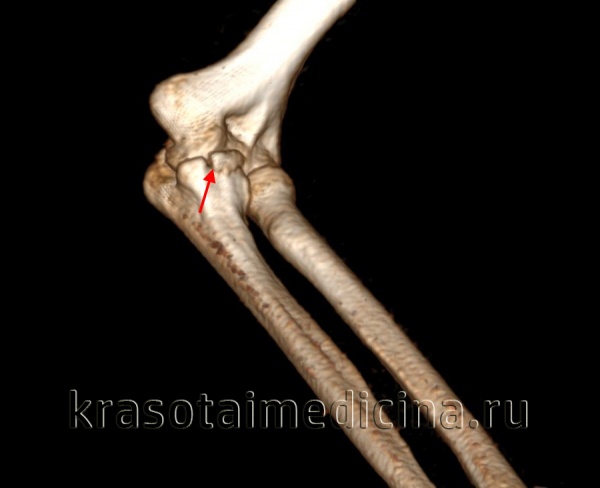

(Справа) На сагиттальной МРТ PDBИ определяется частичный отрыв сухожилия трехглавой мышцы с небольшим оторвавшимся костным отломком МРТ может быть информативна при оценке степени повреждения трехглавой мышцы. (Слева) На сагиттальной КТ с реформатированием можно видеть раздробление локтевого отростка после падения на локтевой сустав. Перелом открывается на суставную поверхность в нескольких местах.

(Справа) На сагиттальной КТ с реформатированием со схемой мягких тканей у этого же пациента визуализируется прикрепление сухожилия трехглавой мышцы и смещение околосуставных жировых подушек. Несмотря на то, что КТ может помочь оценить целостность трехглавой мышцы, МРТ является более точным метом визуализации.

о КТ: сагиттальная с реформатированием для оценки величины щели между суставными поверхностями

о МРТ: сагиттальная и осевая Т2ВИ для оценки перелома и целостности трехглавой мышцы

Боковая проекция локтевого сустава позволяет увидеть перелом локтевого отростка с минимальным смещением без признаков перехода на венечный отросток. Лучеголовчатый и локтевой суставы сохранены. Здесь можно видеть боковую проекцию у этого же пациента. Проведена фиксация стягивающей проволокой. Стягивающую проволоку протянули в виде восьмерки и закрепили двумя спицами Киршнера. При простых переломах локтевого отростка это эффективное лечение, хотя осложнения, связанные с металлоконструкцией, наблюдаются часто. В боковой проекции локтевого сустава определяется сложный перелом дистального конца плечевой кости. Локтевой отросток интактен. Фиксация перелома плечевой кости потребует остеотомии локтевого отростка для доступа к плечевой кости. Здесь можно видеть боковую проекцию у этого же пациента после оперативной репозиции двухмыщелкового перелом плечевой кости. После остеотомии локтевого отростка наложена пластина и выполнена фиксация шурупами.